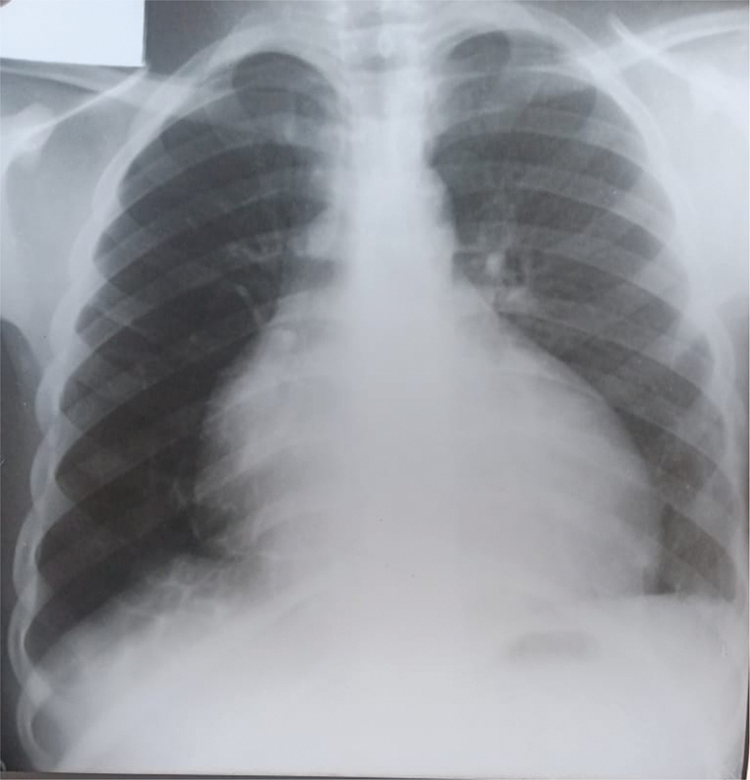

Further review and meticulous physical examination and investigations revealed confused and restless patient, febrile (T = 40°C), pale, acyanosed, RR: 38 breaths/min, SPO2 90%, pulse rate 122/min, blood pressure of 120/40 mmHg, Jugular venous pressure not raised, displaced apex and hyperdynamic, heart sound: S1, S2 and S3 gallop, PSM grade 3/6 loudest at 4th left intercostals space lateral to sternal border, tricuspid PSM grade 1/6 epigastrium, aortic diastolic murmur grade 2/4, bi-basal fine crackles. a provisional diagnosis of congenital heart disease (VSD) with aortic incompetence complicated by infective endocarditis, sepsis, AKI and acute left ventricular HF was entertained with differential diagnosis of Rheumatic heart disease (RHD) with complications. He was started on oxygen therapy and switched from generic ceftriaxone to the branded ceftriaxone (Rocephin). Metronidazole was stopped and gentamicin added adjusted for renal function, he also received furosemide along with conservative renal therapy and close monitoring. Additional relevant investigations were requested which include (1) Laboratory test as indicated in (Table 1b) (2) Electrocardiogram (ECG) which showed sinus tachycardia with heart rate of 115 beat per min (Fig. 1). (3) Chest X-ray (CXR): Showed cardiomegaly of biventricular configuration with cardiothoracic ratio of 0.61, prominent pulmonary vasculature, upward blood diversion and blunted left costophrenic angle (Fig. 2). (4) Transthoracic echocardiography (TTE): revealed interventricular septal thickness of 9.4 mm and left ventricular posterior wall thickness of 13.5 mm. Moderately dilated left ventricle (LV) with internal diameter of 66.4 mm, mildly dilated left atrial with internal of diameter 44.1 mm, mildly dilated right ventricle with internal diameter of 43.9 mm, moderately dilated right atrium with internal diameter of 53.2 mm, Peri-membranous VSD measured 5.3 mm in size with color Doppler demonstrating left to right shunt (Fig. 3A,B). Aortic valve prolapse of the non-coronary cusp 4.5 mm from the plane and severe aortic regurgitation [Width of vena contracta of 7.4 mm and regurgitant jet width/LV out flow tract diameter ratio of 2.1 cm/2.6 cm of 0.80 (80%)] (Fig. 4A,B), large oscillating echogenic mass attached to tricuspid valve leaflet was noted (Fig. 5) and (Supplementary Materials Video S1). LV Ejection fraction (EF) was 64.7% on M-mode guided 2-D with fractional shortening of 36.3% and normal RV systolic function (TAPSE: 20.4 mm). LV end-diastolic volume index was 135.8 mL/m2 (Severely abnormal), while LV end-systolic volume index was 47.9 mL/m2 (Severely abnormal) and LV mass index (LVMI) was 209.3 g/m2 (Severely abnormal). Other heart valves appeared normal in motion and morphology. Moderate mitral regurgitation, severe tricuspid regurgitation and mild pulmonary regurgitation were noted. Pulmonary arterial systolic pressure at rest was 52.2 mmHg.

Figure 2: CXR showing cardiomegaly of biventricular configuration, pulmonary vascular engorgement, upwards blood diversion and blunted left costophrenic angle